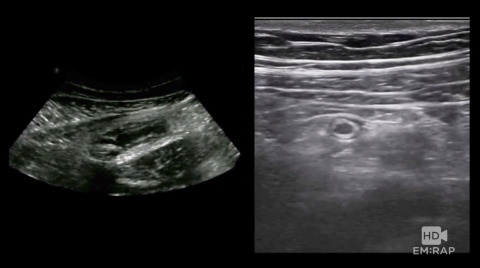

Ultrasound of Appendicitis

How to do a Point of Care Ultrasound (POCUS) to assess for appendicitis. Presented by Dr. Jacob Avila, MD.